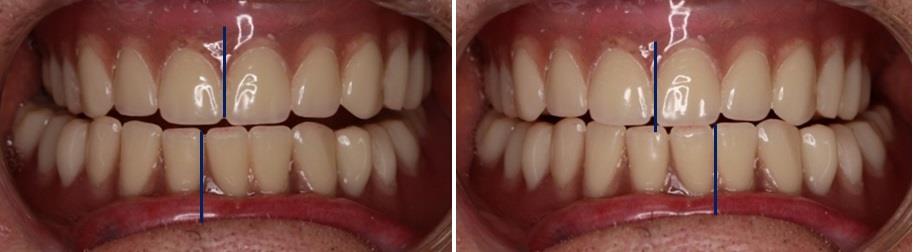

В приведенном примере окклюзионный статус пациента не соответствовал оптимальной норме и характеризовал одностороннюю перекрестную окклюзию со смещением верхних жевательных зубов в язычную (нёбную) сторону (рис. 4).

Рис. 4. Состояние окклюзии после протетического лечения